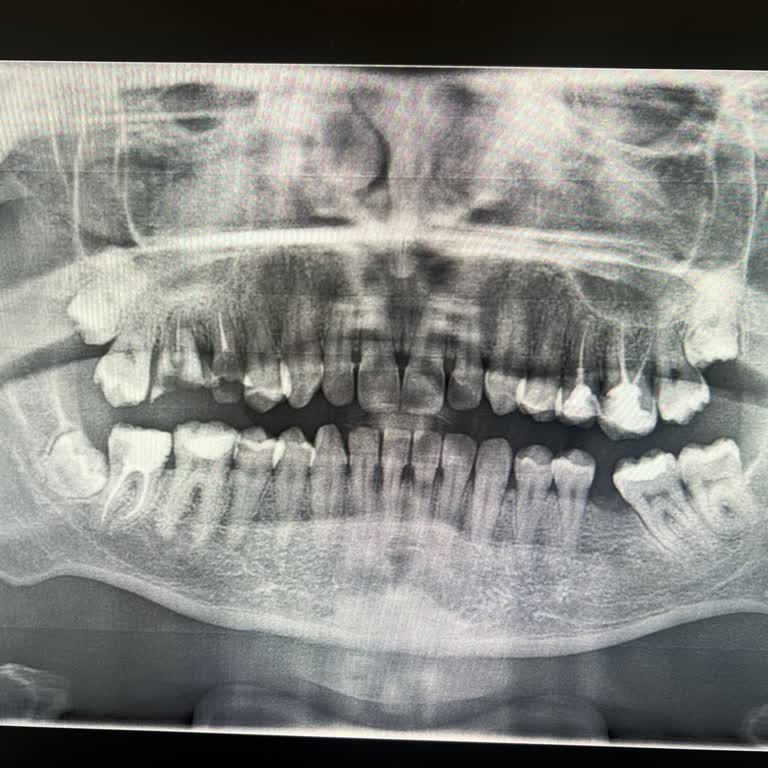

09.04.2026 günü saat 13:35 civarında Beykent Üniversitesi Diş Hastanesi’ne kırık olan bir dişim için muayeneye gittim. Doktor, kırık olan bu dişimin çekileceğini, ayrıca sağ tarafta en arkadaki bir dişimde kök sorunu olduğunu söyleyip onun da çekilmesi gerektiğini belirtti. Ben de üst tarafta sorunl...